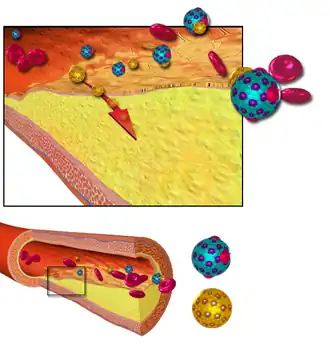

Early atherogenesis is characterized by the adherence of blood circulating monocytes (a type of white blood cell) to the vascular bed lining, the endothelium, then by their migration to the sub-endothelial space, and further activation into monocyte-derived macrophages.[9][67] The primary documented driver of this process is oxidized lipoprotein particles within the wall, beneath the endothelial cells, though upper normal or elevated concentrations of blood glucose also plays a major role and not all factors are fully understood. Fatty streaks may appear and disappear.

Low-density lipoprotein (LDL) particles in blood plasma invade the endothelium and become oxidized, creating risk of cardiovascular disease. A complex set of biochemical reactions regulates the oxidation of LDL, involving enzymes (such as Lp-LpA2) and free radicals in the endothelium.[68]

Initial damage to the endothelium results in an inflammatory response. Monocytes enter the artery wall from the bloodstream, with platelets adhering to the area of insult. This may be promoted by redox signaling induction of factors such as VCAM-1, which recruits circulating monocytes, and M-CSF, which is selectively required for the differentiation of monocytes to macrophages. The monocytes differentiate into macrophages, which proliferate locally,[69] ingest oxidized LDL, slowly turning into large "foam cells" – so-called because of their changed appearance resulting from the numerous internal cytoplasmic vesicles and resulting high lipid content. Under the microscope, the lesion now appears as a fatty streak. Foam cells eventually die and further propagate the inflammatory process.

In addition to these cellular activities, there is also smooth muscle proliferation and migration from the tunica media into the intima in response to cytokines secreted by damaged endothelial cells. This causes the formation of a fibrous capsule covering the fatty streak. Intact endothelium can prevent this smooth muscle proliferation by releasing nitric oxide.

Cholesterol is delivered into the vessel wall by cholesterol-containing low-density lipoprotein (LDL) particles. To attract and stimulate macrophages, the cholesterol must be released from the LDL particles and oxidized, a key step in the ongoing inflammatory process. The process is worsened if it is insufficient high-density lipoprotein (HDL), the lipoprotein particle that removes cholesterol from tissues and carries it back to the liver.[68]

The foam cells and platelets encourage the migration and proliferation of smooth muscle cells, which in turn ingest lipids, become replaced by collagen, and transform into foam cells themselves. A protective fibrous cap normally forms between the fatty deposits and the artery lining (the intima).